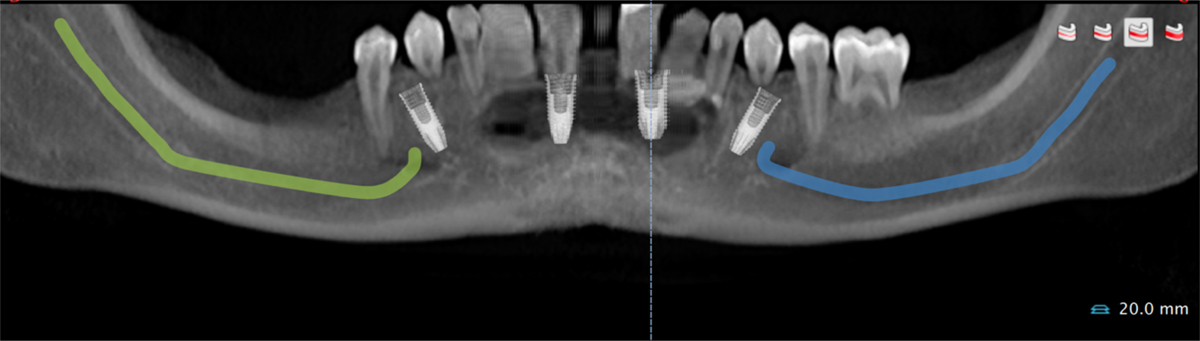

Digital planning of four mandibular implants (All-on-4) using DTX Studio Nobel® software.